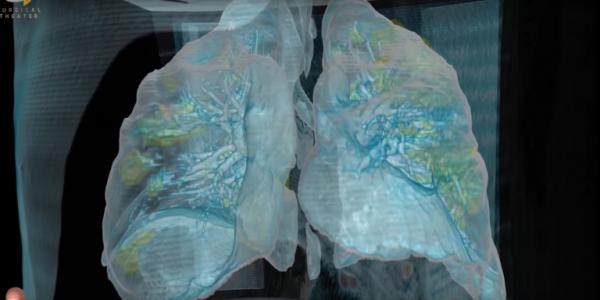

Σύστημα τεχνητής νοημοσύνης κάνει ακριβείς διαγνώσεις παθήσεων [Βίντεο]

Αμερικανοί και Κινέζοι επιστήμονες ανέπτυξαν ένα νέο σύστημα τεχνητής νοημοσύνης που μπορεί να κάνει με ταχύτητα και ακρίβεια διαγνώσεις των παθήσεων των ματιών και των πνευμόνων.